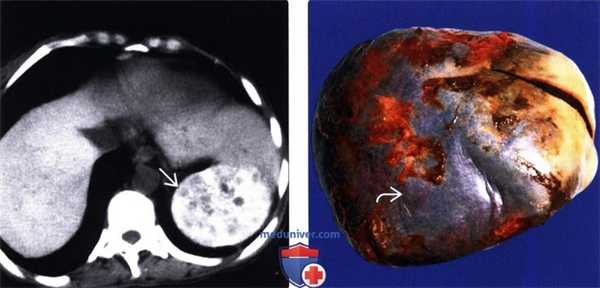

(Левый) При КТ без контрастирования на аксиальной томограмме визуализируется интенсивно кальцинированная гетерогенная селезенка; такие изменения указывают на хронический и, возможно, острый инфаркты.

(Правый) После спленэктомии на макропрепарате наблюдается крапчатость селезенки и диспигментация капсулы, при гистологическом исследовании отмечался тяжелый кальциноз тканей.